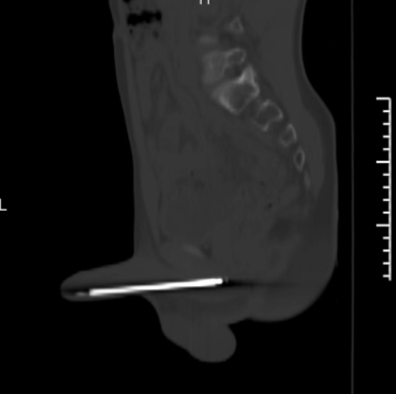

近日,国家区域医疗中心上海儿童医学中心贵州医院儿童泌尿外科急诊收治了一名尿道异物的患儿。12岁的洋洋(化名)因为好奇,将一根12cm长的粉刺针插入自己的阴茎尿道,随后,出现了阴茎疼痛,排尿不适等症状。

据洋洋的手术医生儿童泌尿外科占雄副主任医师介绍,术中,发现粉刺针整体卡在洋洋尿道里,虽然还未进入膀胱,但是尖端已刺入尿道粘膜。

由于粉刺针较粗,常规的异物钳无法夹取,情况较为棘手。如果采用传统尿道切开取物术,会给孩子造成巨大创伤,术后并发症较多,恢复时间也长;而选择微创方式,通过腔镜经尿道取出,却同样面临挑战:12岁男孩尿道较长,尿道黏膜娇嫩,粉刺针尖端非常尖锐,操作稍有不慎就容易刺穿尿道。